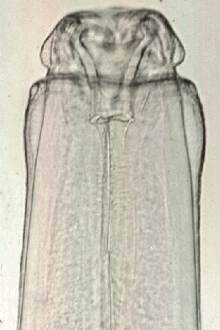

Le genre Habronema appartient à la sous-famille des Spirurinés, à la famille des Spiruridés et à l'ordre des Nématodes. Les mâles mesurent de 8 à 22 mm de long et les femelles de 13 à 35 mm selon les espèces. Ce sont des parasites spécifiques des équidés.

Photo Laboratoires Mérial

Photos Laboratoires Mérial